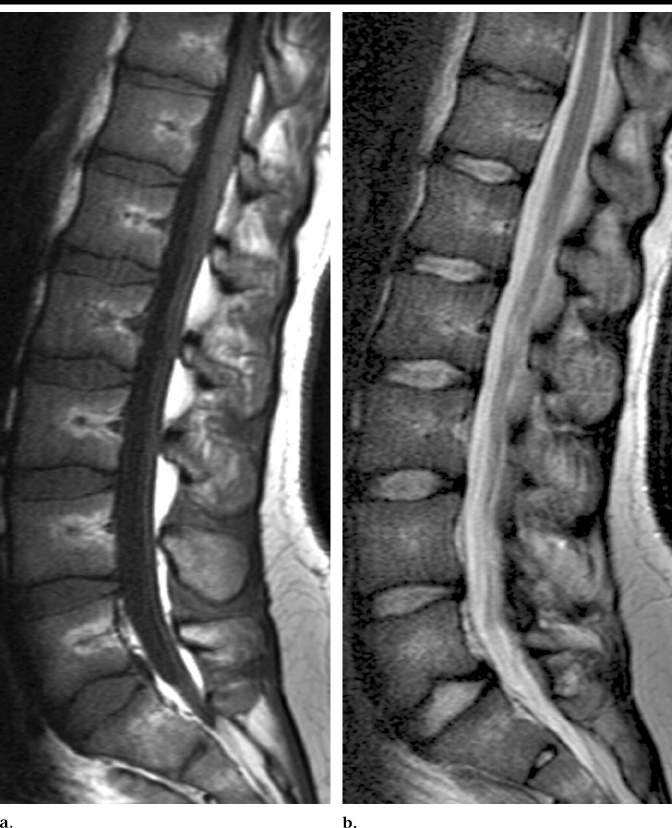

Minh họa và tiêu chuẩn phân loại mức

-

Ảnh MRI mặt cắt sagittal sẽ cho thấy rõ các lỗ liên hợp.

Ảnh bên trái minh họa lát cắt MRI với các lỗ liên hợp được đánh dấu bằng dấu cộng.

Ảnh bên phải minh họa tiêu chuẩn phân loại mức độ chèn ép (grading criteria):

Normal/Mild (Bình thường/nhẹ)

Moderate (Trung bình)

Severe (Nặng)

(Lưu ý: Trong thử thách này, Normal/Mild được gộp thành một nhãn duy nhất.)